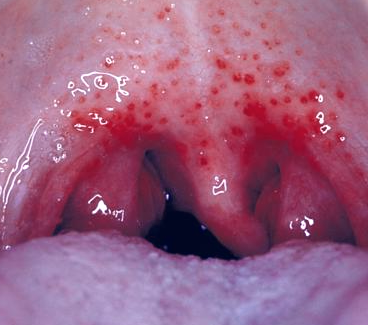

Common Causes of Red Spots on Roof of Mouth | IYTmed.com

Bumps in Back of Throat, Raised, Little, White, Red, Itchy …